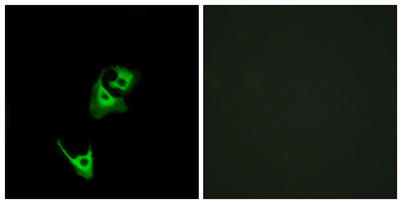

Product name: GLP-1R rabbit pAb

Dilutions: Western Blot: 1/500 - 1/2000. Immunofluorescence: 1/200 - 1/1000. ELISA: 1/5000. Not yet tested in other applications.

Cellular localization: Cell membrane ; Multi-pass membrane protein .